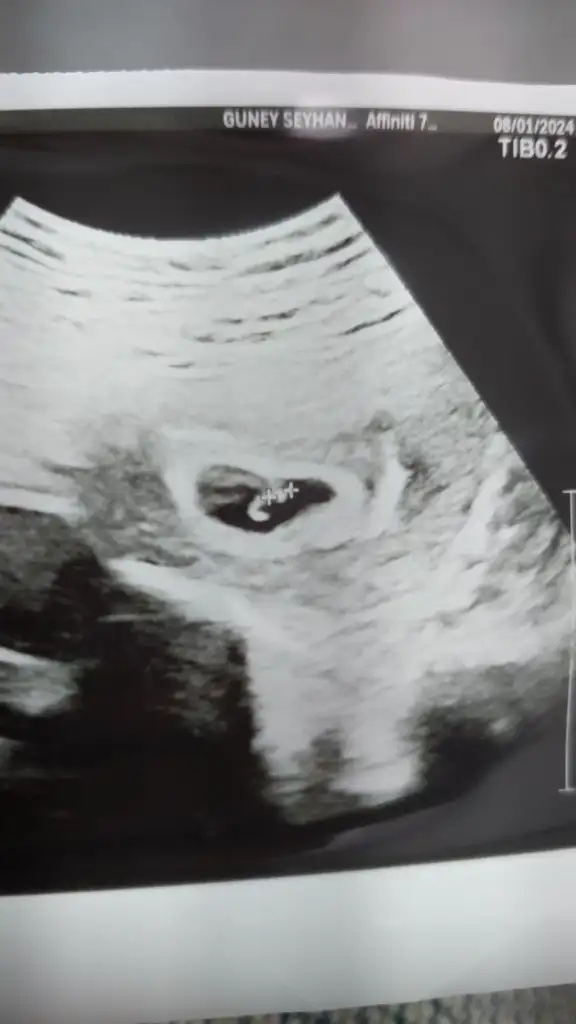

Merhaba bence kız, sağlıkla gelsin inşallahBizi de yorumlarmısınız 6+6 günlük vajinal usg

Merhaba cinsiyeti öğrendiniz mi benim ultrasonda aynı merak ettimBizi de yorumlarmısınız 6+6 günlük vajinal usg

Merhaba arkadaşa kız demiştim tahminim o yönde siz ogrendiniz mı? Sizin de kızdır vajinal ultrasonsa ve benzer pozisyondaysa.Kucaginiza almak nasip olsun inşallahMerhaba cinsiyeti öğrendiniz mi benim ultrasonda aynı merak ettim

Şuan 10 haftalık ben çok karşılaştırma yaptım benim ultrason normal karından ultrason gibi gosterilmisMerhaba arkadaşa kız demiştim tahminim o yönde siz ogrendiniz mı? Sizin de kızdır vajinal ultrasonsa ve benzer pozisyondaysa.Kucaginiza almak nasip olsun inşallah

Mrb bugün öğrendik kızMerhaba cinsiyeti öğrendiniz mi benim ultrasonda aynı merak ettim